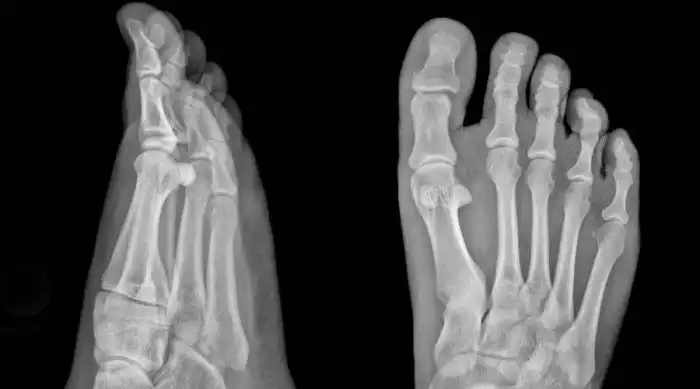

Доведенное до третьей степени плоскостопие приводит к серьезной деформации стопы. Отеки появляются ежедневно, ходить становится трудно даже в пределах комнаты. Теперь без ортопедических ботинок обойтись не получится, иначе будет только хуже.